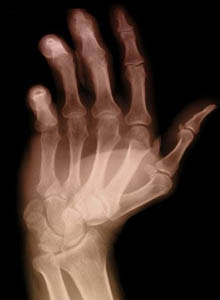

L’artrite reumatoide è una malattia infiammatoria cronica, tendente a persistere nel tempo, che interessa tutto l’organismo e non solo alcune articolazioni.

È una malattia ciclica, con fasi di acutizzazione intervallate a periodi di remissione dei sintomi. Determina dolore e rigidità articolare soprattutto al mattino.